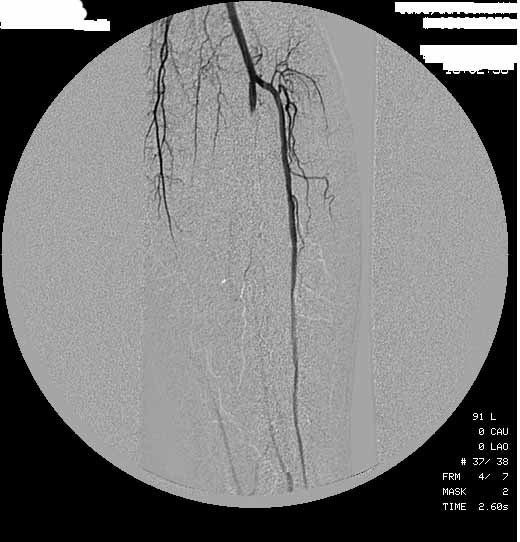

Хочу показать снимки одной из наших пациенток с кртической ишемией. (Оговорюсь - все прооперированные у нас паиенты были с явлениями критической ишемии или наличием трофических дефектов стоп иешмического гененеза)

Вложение:

? ?€????“? ?±1.jpg

? ?€????“? ?±1.jpg [ 53.93 | Просмотров: 30673 ]

? ?€????“? ?±2.jpg

? ?€????“? ?±2.jpg [ 53.07 | Просмотров: 30673 ]

? ?€????“? ?±3.jpg

? ?€????“? ?±3.jpg [ 53.73 | Просмотров: 30673 ]

Как видно на снимках боковые ветви есть.